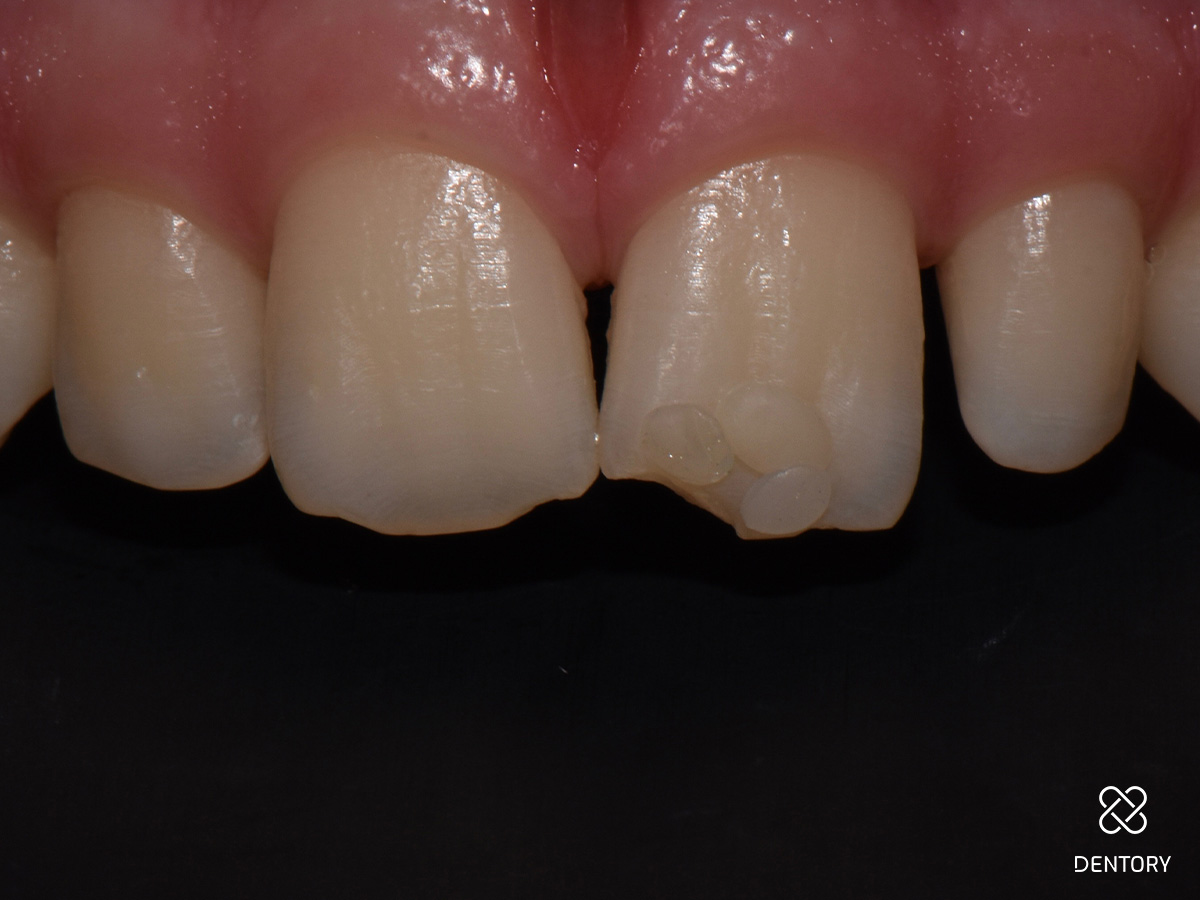

Die Füllung hat sich harmonisch in die Umgebung integriert. Trotz der minimalistischen Gestaltung hat sich ein dezenter Halo-Effekt ergeben.

Abbildung 12

Kontrolle nach 14 Tagen Kleine Füllungsrestaurationen im Frontzahnbereich können sich aufgrund vielfältiger Effekte besonders im Inzisalkanten-Bereich als schwierig erweisen. Dieser Fall zeigt aber, dass bei einer korrekten Farbauswahl sowie Form- und Texturgebung auch ohne komplizierte Methoden zuverlässige Ergebnisse erzielt werden können.